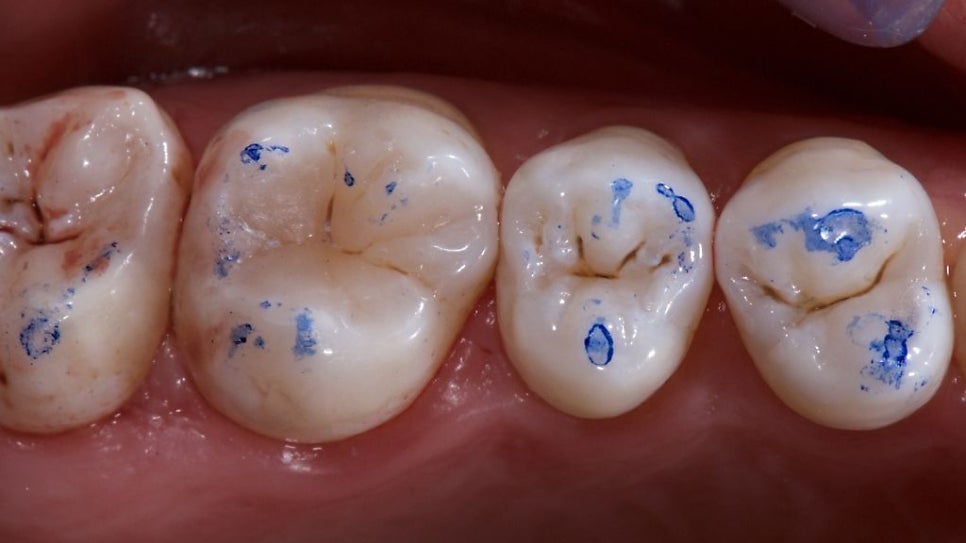

위 사진에서 치아에 점이 찍힌 부분이 씹을때 닿는 부분입니다. 이런 부분들 중에 특정 부분이 특별히 많이 닿거나 하게되면 그 부분이 높다고 할 수 있어요. (출처: https://www.styleitaliano.org/)

치과에 가시면 "딱딱 씹어보세요~" 하는 경험 많이 해보셨죠 ㅎㅎ 위 사진같이 교합지(Articulating Paper)을 사용해서 씹을때 치아의 어느부분이 높은지 파악할 수 있습니다. (출처: https://www.nature.com/)